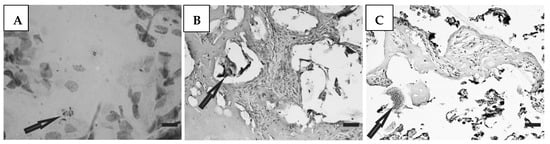

3.5. Histological Studies

Histological preparations of placental tissue sections representative of non-transmitter and transmitter mothers are shown in Figure 2 and Figure 3. Different forms of the parasite were detected through the microscopic observation of chorionic villous human placenta from these mothers. Amastigote nests were observed in preparations from non-transmitter (Figure 2A,B) and transmitter (Figure 3A) mothers, while released parasites were found in placentas from non-transmitter (Figure 2C) and transmitter (Figure 3B,C) mothers.

Figure 2.

Histological section of the placenta from a non-transmitter mother. Arrows point to (A,B) amastigote nests; and (C) released parasites (H&E). Scale bar: 25 μm.